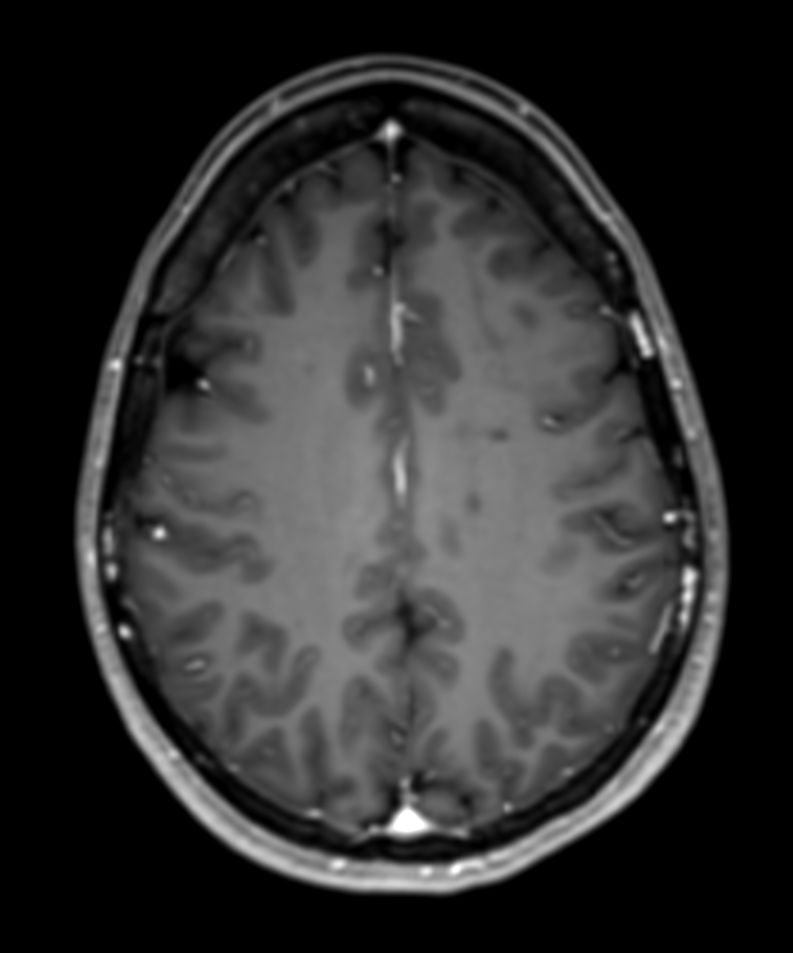

SWI sequence has a high sensitivity to enhance contrast for deoxygenated (venous) blood or calcium deposits. This may help, when used in combination with other clinical information, in the diagnosis of various neurological pathologies. 3D imaging lets you acquire high resolution data in multiple directions in one scan. Isotropic voxel size enables reformats in any plane without loss of resolution. FLAIR* requires offline post processing combining the contrast of 3D FLAIR and 3D SWI EPI into a single image. This enables the visualization of Central Vein Sign, mapping subcortical veins onto 3D FLAIR contrast images.